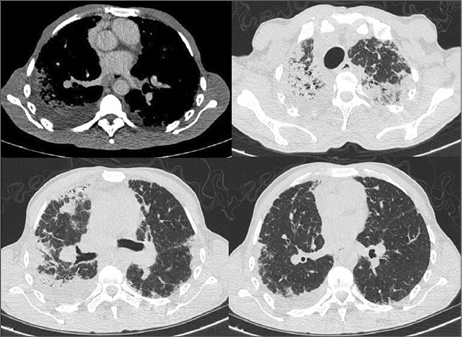

Ingresó por neumonía. Tomografía (TC) de tórax (Figura 1) mostró disminución volumétrica de lóbulo superior derecho, con engrosamiento intersticial, consolidaciones y bronquiectasias por tracción en ambos lóbulos superiores, compromiso intersticial en lóbulos inferiores, derrame pleural derecho. Lavado bronquiolo-alveolar: Pseudomonas Aeruginosa; se descartó tuberculosis y hongos. Resuelto el cuadro infeccioso, mantuvo disnea y crepitantes tipo velcro.

Caso 1. TC inicial. Disminución volumétrica de lóbulos superiores a predominio derecho. Engrosamiento del intersticio bilateral de tipo reticular, a predominio subpleural, asociado a consolidaciones y bronquiectasias por tracción en lóbulos superiores. Derrame pleural derecho.

TC de control (Figura 2): neumotórax y progresión del compromiso intersticial. Espirometría: patrón restrictivo severo, capacidad vital forzada (CVF): 35%.

Caso 1. TC en evolución. Progresión de los cambios fibróticos, neumotórax derecho de moderada entidad, con engrosamiento pleural.